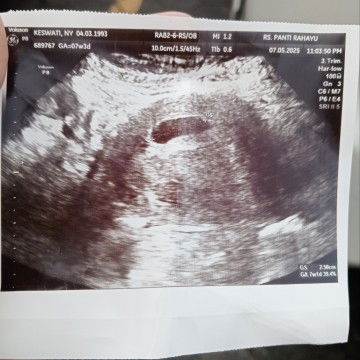

Sudah kehamilan 7minggu tapi hnya terlihat kantong,Janinya belum kelihatan ?

Kehamilan ke 3 tapi masih was2

kata dokternya gmn bun? biasanya nunggu seminggu atau 2minggu disuruh USG lagi